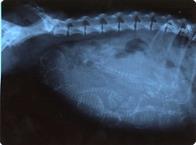

Week 8

The pups have fur and are crowded in the uterus. You may see a lot of movement as the pups get in position for birth.